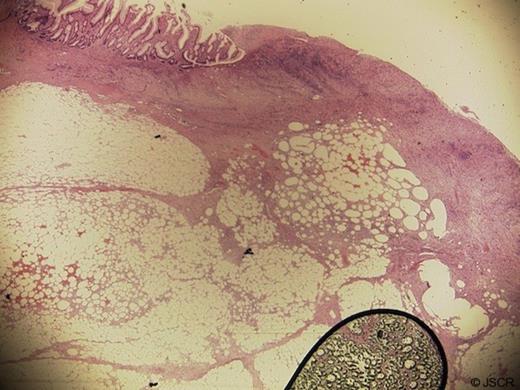

A laparoscopic extended right hemicolectomy was performed under general anaesthesia. The lesion was marked preoperatively allowing identification laparoscopically. There were no complications and the patient made an excellent recovery and was discharged home. He remains well at follow-up. Gross and Microscopic histological examination showed a submucosal lipoma with areas of fat necrosis and surface ulceration with extensive granulation tissue. This was distortion of the muscularis propria (Figures 3–5). Twelve lymph nodes showed reactive change only. The margins showed normal mucosa.

Gross slices of the tumour show adipose tissue expanding the submucosa. There are areas of fat necrosis and mucosal ulceration

Microscopy shows lobules of mature adipocytes. There is extensive surface ulceration with underlying granulation tissue and areas of fat necrosis